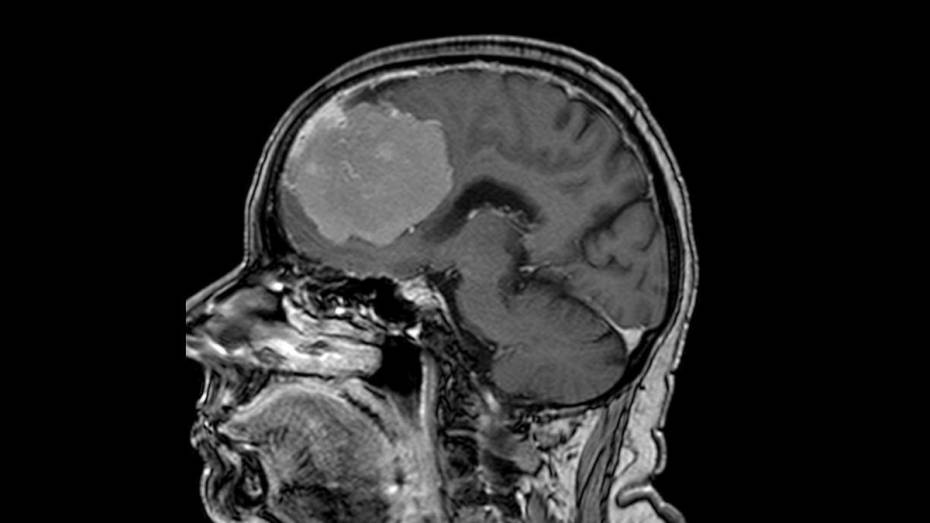

Нейрохирурги Воронежской городской больницы скорой медицинской помощи (БСМП) №1 провели 80-летней пациентке сложную 6-часовую операцию по удалению опухоли мозга, которая достигла размеров грейпфрута – 6 х 7 х 8 см. Главной задачей врачей было не только удалить новообразование, но и сохранить здоровье пожилой женщины – не повредить жизненно важные сосуды и участки мозга, чтобы избежать осложнений. Медиков ждал успех. Сейчас пациентка уже выписана, послеоперационный период у пенсионерки проходит хорошо, она обслуживает себя самостоятельно. Неврологическая симптоматика спала сразу после хирургического вмешательства. Об этом случае рассказали в региональном министерстве здравоохранения в среду, 21 мая.

Пенсионерка поступила в БСМП №1 с подозрением на инсульт. У женщины наблюдались проблемы с речью и слабость в правой руке. После стандартного обследования с помощью компьютерной томографии выяснилось, что инсульта у нее нет. Однако в обеих лобных долях мозга была обнаружена опухоль.

– Подобные новообразования так или иначе затрагивают важные участки мозга – кровеносные сосуды и зоны, отвечающие за речь и движение. Дополнительное исследование с контрастом показало, что опухоль окутывала магистральные сосуды Виллизиева круга – переднюю мозговую артерию, а также прорастала в переднюю треть сагиттального синуса (один из наиболее крупных венозных коллекторов головного мозга) и закрывала его, – разъяснили медики.

Команда нейрохирургов тщательно планировала действия с помощью специальной навигационной системы. В ходе операции врачи удаляли опухоль миллиметр за миллиметром и смогли полностью от нее избавиться, сохранив все важные сосуды. Операцию провела команда медиков: